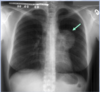

What is the red arrow indicating?

Is this a normal finding on a CXR?

A

• Gastric bubble

• This is a normal finding on a CXR

Free air: Instead of the air being contained inside the stomach to the unitlateral side of the diaphgram, air will be displaced bilaterally on both sides of the diaphragm.